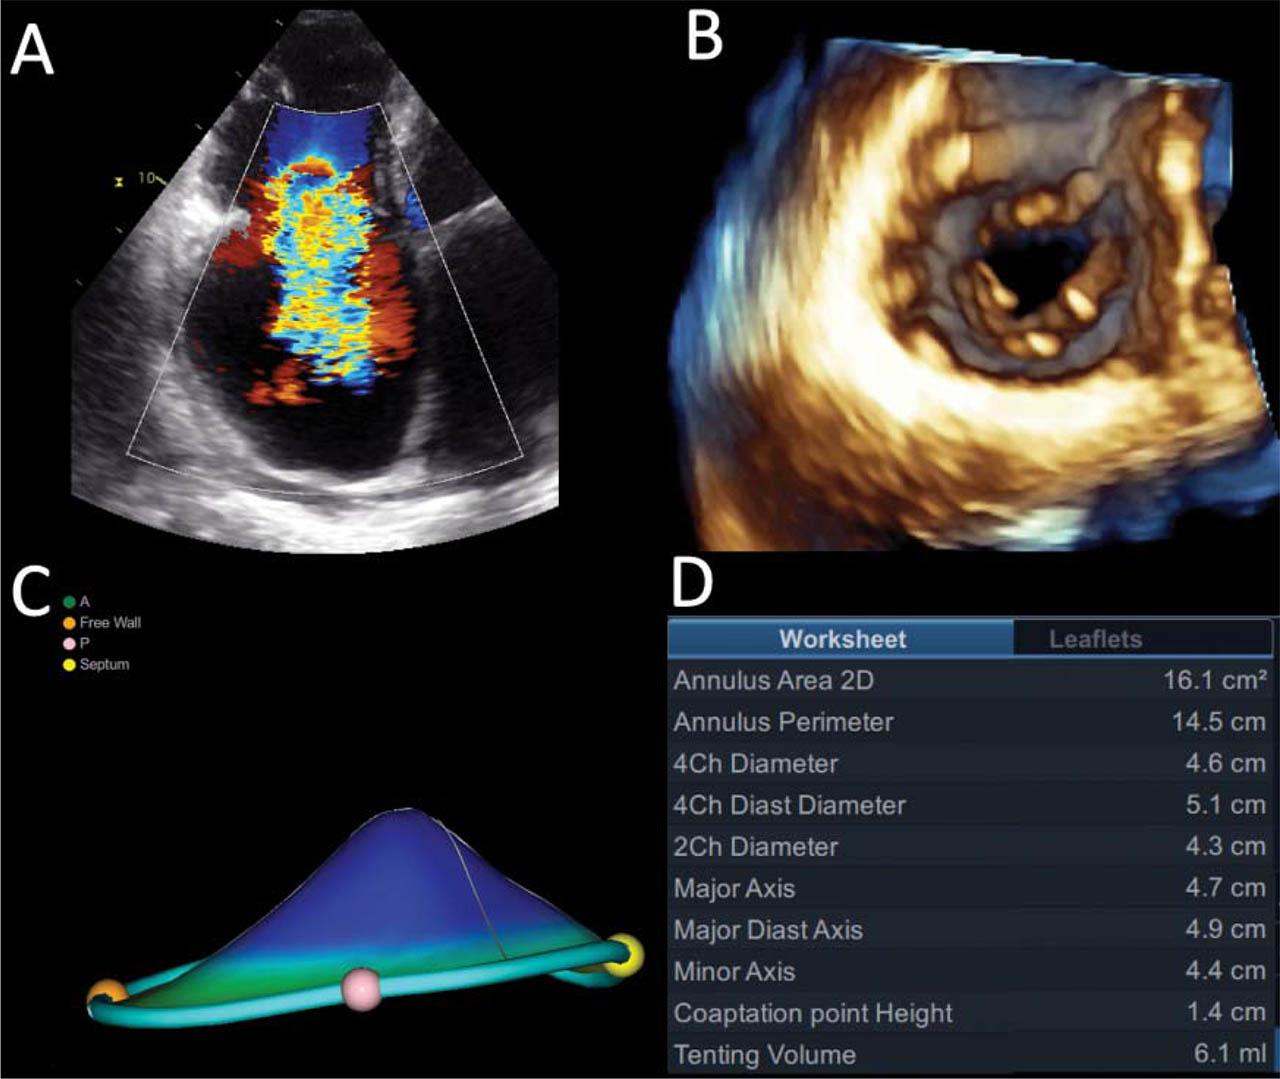

Figure 3

Ventricular functional tricuspid regurgitation in a patient with pulmonary hypertension. RV-focused apical four-chamber color flow of the regurgitant jet (A); En face view of the tricuspid valve by three-dimensional echocardiography (B); Tricuspid annulus geometry (C) and measurements (D) by 4D Auto TVQ software (GE Healthcare, Horten, N). Note the significant leaflet tethering (coaptation point height, tenting volume) with respect to Figure 2.